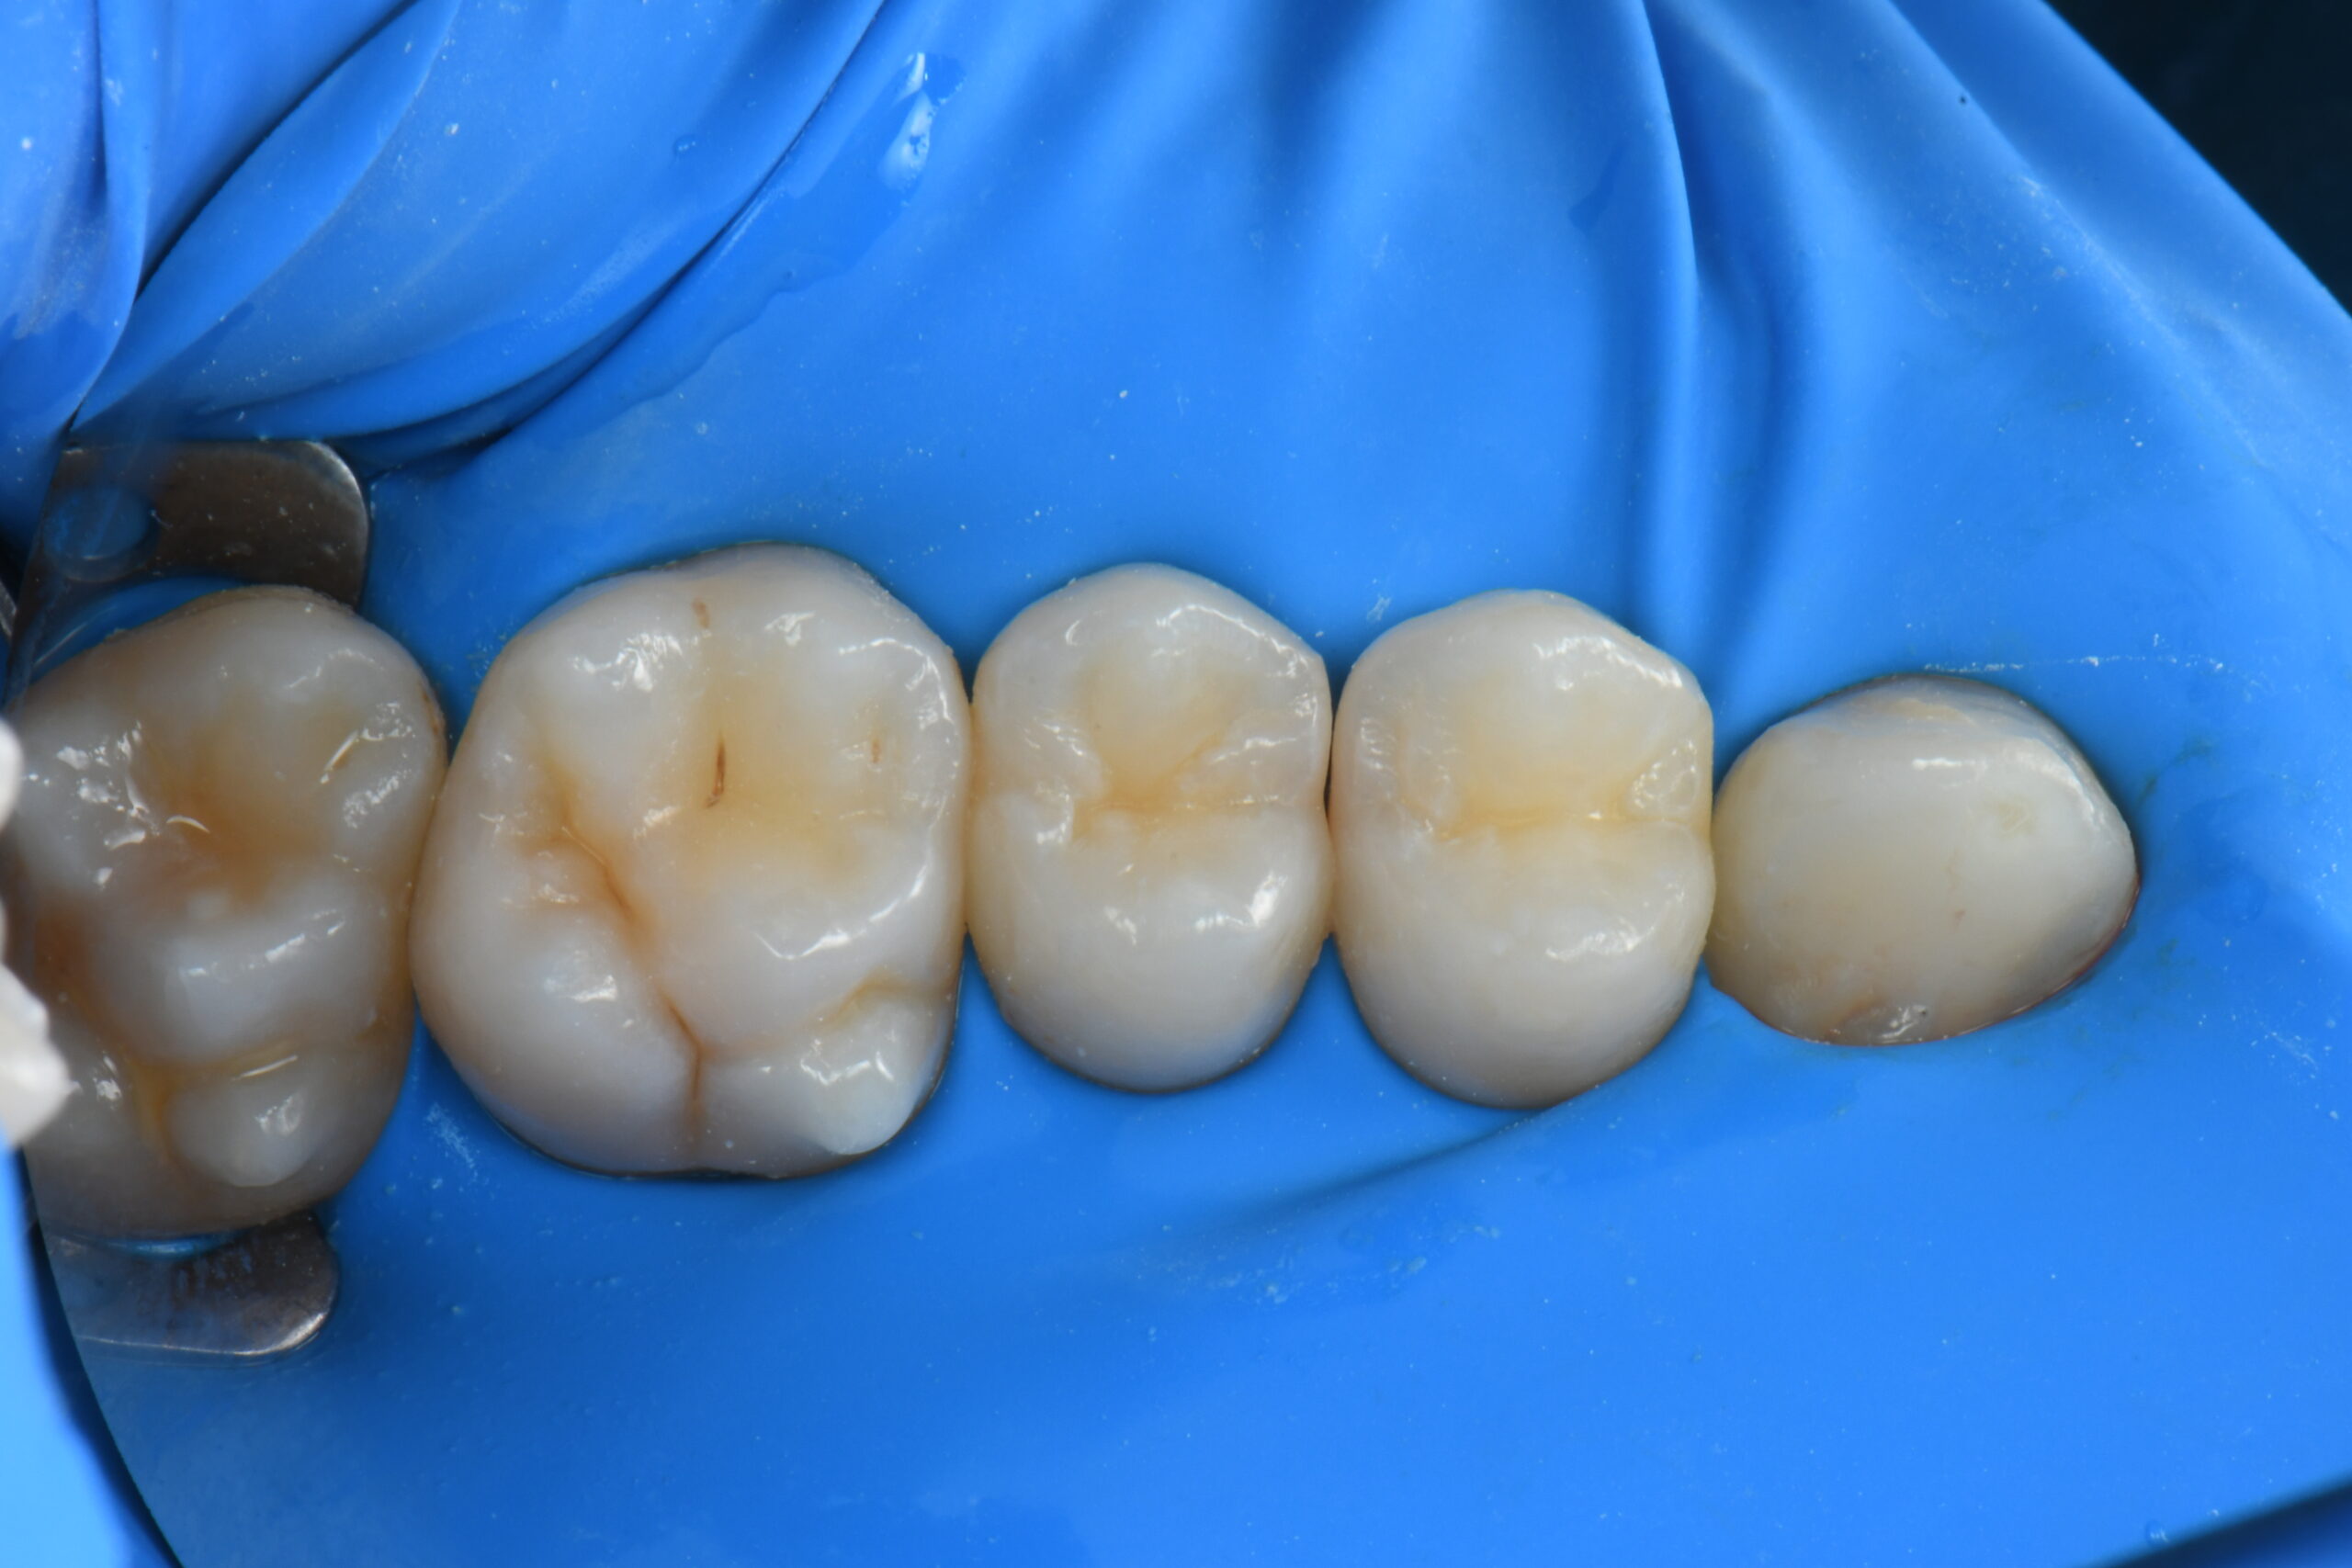

Five molar teeth isolated with a blue dental dam

The rubber dam is properly placed.